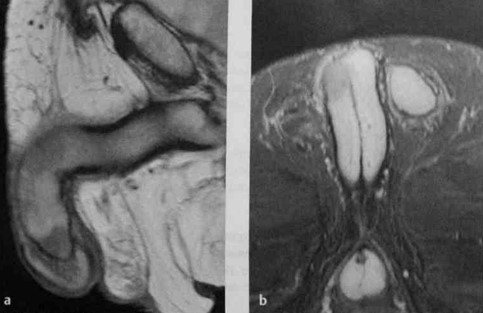

a, b Два метастаза переходноклеточного рака; один по дорсальной поверхности кавернозного тела в средней части полового члена, другой прилежит к головке полового члена. Сагиттальная Т1-взвешенная МРТ в режиме TSE (а) и аксиальная Т2-взвешенная МРТ в режиме IR (b). Метастазы можно определить по более низкой интенсивности сигнала по сравнению с кавернозными телами.